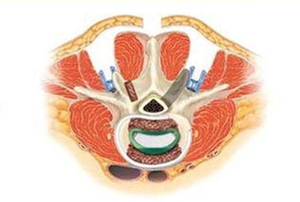

因此,脊柱外科医生在传统融合手术基础上逐渐探索,发现通过肌肉间隙入路进入手术区域可以大大减少血管以及神经的损伤,不仅可以减少术中出血、术后引流,由于肌肉损伤少,术后肌肉退变以及慢性腰痛的发生率也出现明显下降。这缩短了手术时间、减少了肌肉损伤、缓解了术后腰痛症状,进而减少了患者康复所需要的时间。更符合现在快速康复外科的理念。特别是当传统手术术中出血动不动就是200ml,术后总引流在200ml左右的情况下;术中出血几乎在100ml以内,术后引流在50ml左右的肌间隙入路下的腰椎融合手术越来越受到脊柱外科医生的欢迎。